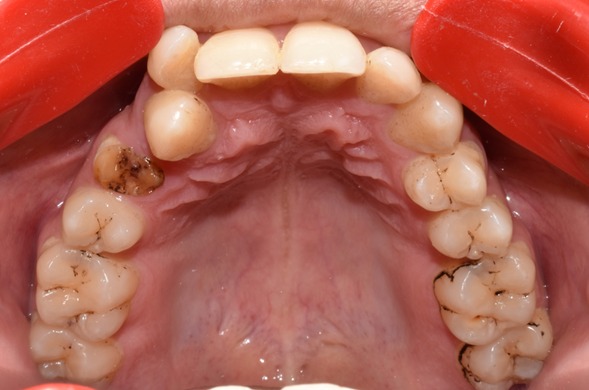

Before & After Results

At Aline Dent, we take pride in delivering visible and lasting improvements in our patients’ smiles. Our before-and-after results highlight the effectiveness of modern dental treatments combined with personalized care. This gallery showcases real dental cases treated at our clinic, giving you a clear idea of how different dental concerns can be corrected with the right treatment approach.

From minor corrections to complete smile enhancements, these teeth transformation results demonstrate how professional dental care can improve both oral health and appearance. Our experienced dental team carefully evaluates each patient’s needs and creates customized treatment plans to achieve natural, healthy, and confident smiles.

In this gallery, you will find a variety of smile makeover cases, including treatments for crooked teeth, gaps, discoloration, damaged teeth, and other common dental concerns.